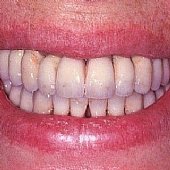

• Die Lachinie der fertigen festsitzenden Versorgung mit Keramikbrücke.

• Die Lachlinie der fertigen festsitzenden Versorgung.

Die Lachinie der fertigen festsitzenden Versorgung mit Keramikbrücke.